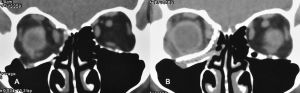

Postoperative imaging of orbital implants

Imaging of orbital fractures is indicated postoperatively to ensure accurate placement of orbital implants, occasionally when postoperative complications arise and when revision surgery is planned. This not only helps identify positioning of implants, but also assess orbital volume and soft tissue consequences and also guide additional surgery when indicated. While metallic implants are radioopaque and easily visible (figure 13 and 14) and easily visualized on bone and soft tissue windows, porous polyethylene implants and bioresorbable implants are more radiolucent and better visualized in soft tissue windows (Figure 15). Examples of suboptimal and good reconstruction with implant characteristics are shown below (Figure 16 and 17).